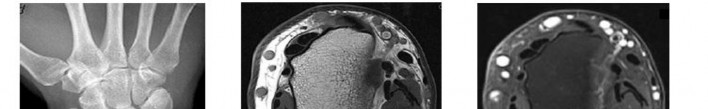

A 45-year-old manual laborer complains of chronic radial-sided wrist pain. He recalls a severe 'sprain' 10 years ago. Radiographs demonstrate scapholunate dissociation with advanced radioscaphoid arthritis. MRI confirms the radiolunate joint is spared, but the proximal capitate shows severe, full-thickness chondral wear.

Which of the following procedures is most appropriate to provide durable pain relief while preserving motion?

Explanation

The patient has Scapholunate Advanced Collapse (SLAC) pattern of the wrist. Stage III SLAC involves the capitolunate joint, while the radiolunate joint characteristically remains spared. Because the capitate head is severely arthritic, Proximal Row Carpectomy (PRC) is contraindicated, as it relies on a healthy cartilage interface between the capitate and the lunate fossa. Scaphoid excision with four-corner fusion (capitate, hamate, lunate, triquetrum) is the procedure of choice.